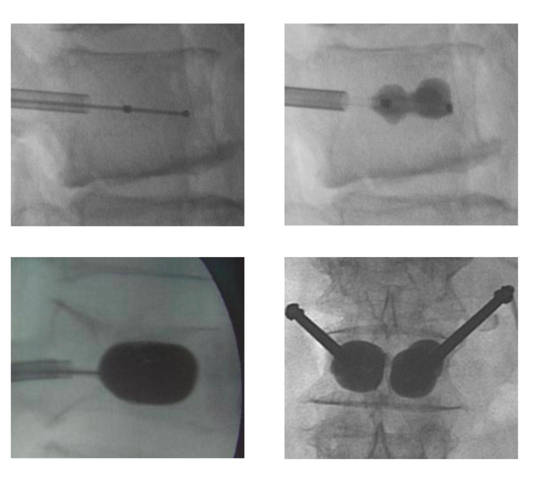

La cifoplastia con balón consiste en introducir en la vértebra fracturada un balón que se infla al inflarse el balón compactamos el hueso que queda en la vértebra y recuperamos la altura de la vértebra, posteriormente se retira el balón rellenándose el hueco que deja con un cemento. El cemento se introduce en un estado viscoso endureciéndose a los 10-15 minutos.